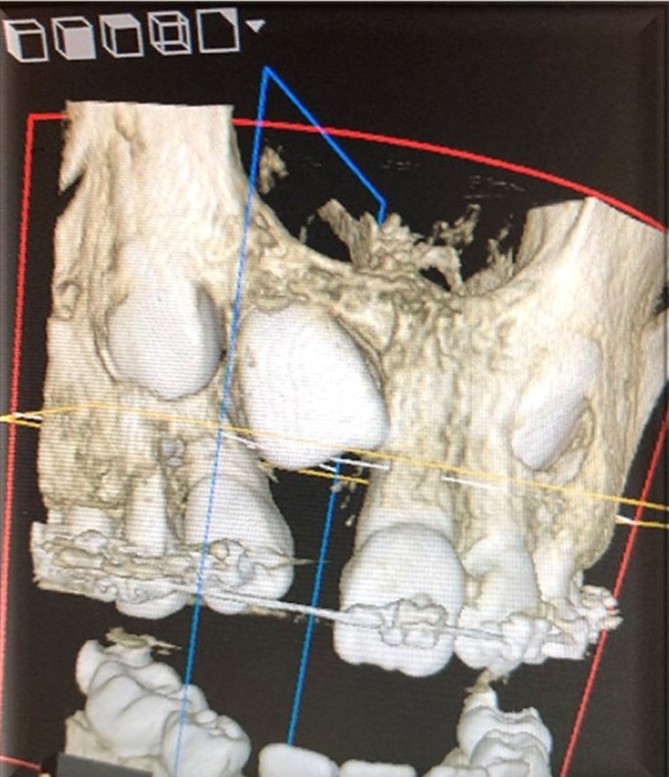

A series of radiographs can be taken to locate its position, but the 3-D Cone beam CT is superior in determining the location of the impacted canine. 4

All patients require a thorough clinical evaluation. The radiographic evaluation should include a panoramic radiograph and a 3-D CBCT to evaluate the tooth position and condition of the lateral incisor root. Then, a comprehensive treatment plan can be developed. Informed consent is a must to avoid misunderstanding, which could lead to legal problems. Management of the impacted canine can include one of the following treatment options:

The 3-D CBCT is considered the standard and has proven superior to other radiographic methods. (Fig.4)

A 3-D CBCT is the best radiograph to see the exact position of the impacted tooth. Understanding the tooth’s proximity to important anatomic structures (mental foramen, maxillary sinus) helps to choose the best surgical approach to exposing the impacted tooth. It is important to show the orthodontist the technical difficulty of bringing the tooth into the arch.